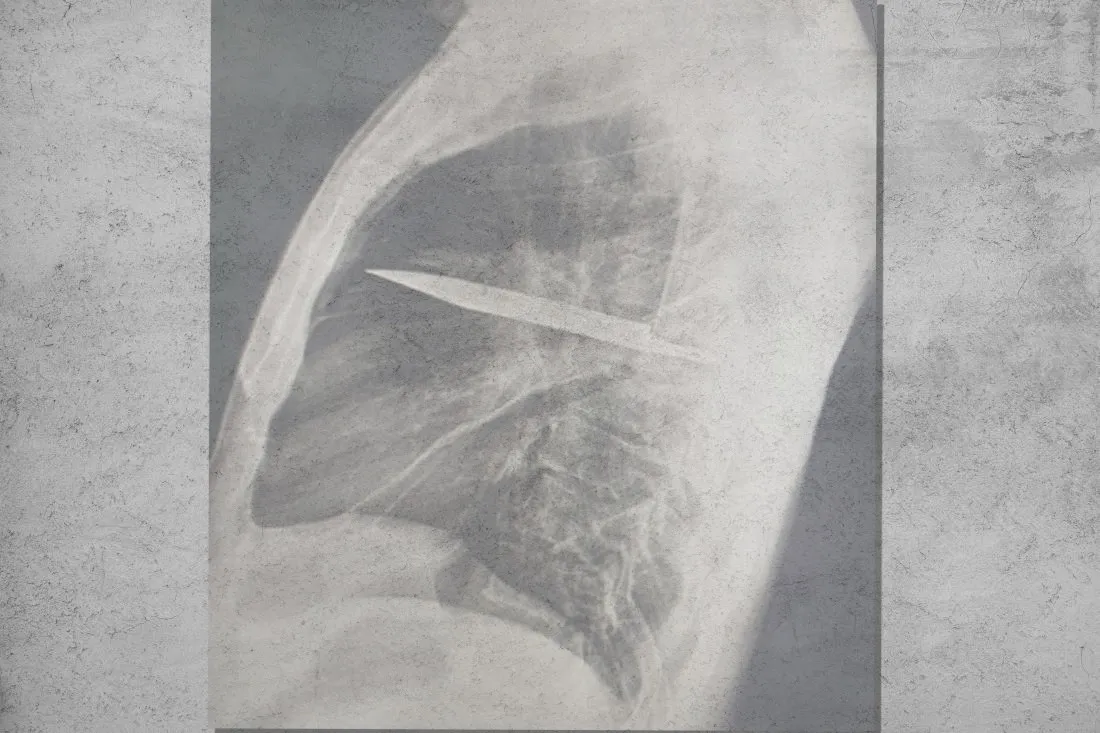

Наконец, сделав рентген, доктора увидели страшную картину: глубоко в грудной клетке пациента оказался спрятан кусок металла, покрытый гноем и омертвевшими тканями. Оказалось, что это нож, попавший туда ещё восемь лет назад во время той самой потасовки.

Пациента экстренно положили на операционный стол, хирурги успешно извлекли нож, а спустя десять дней больной поправился и отправился домой. Доктора подчёркивают, что мужчине крупно повезло: оставшись незамеченным, посторонний предмет рано или поздно вызвал бы необратимые последствия и смерть.